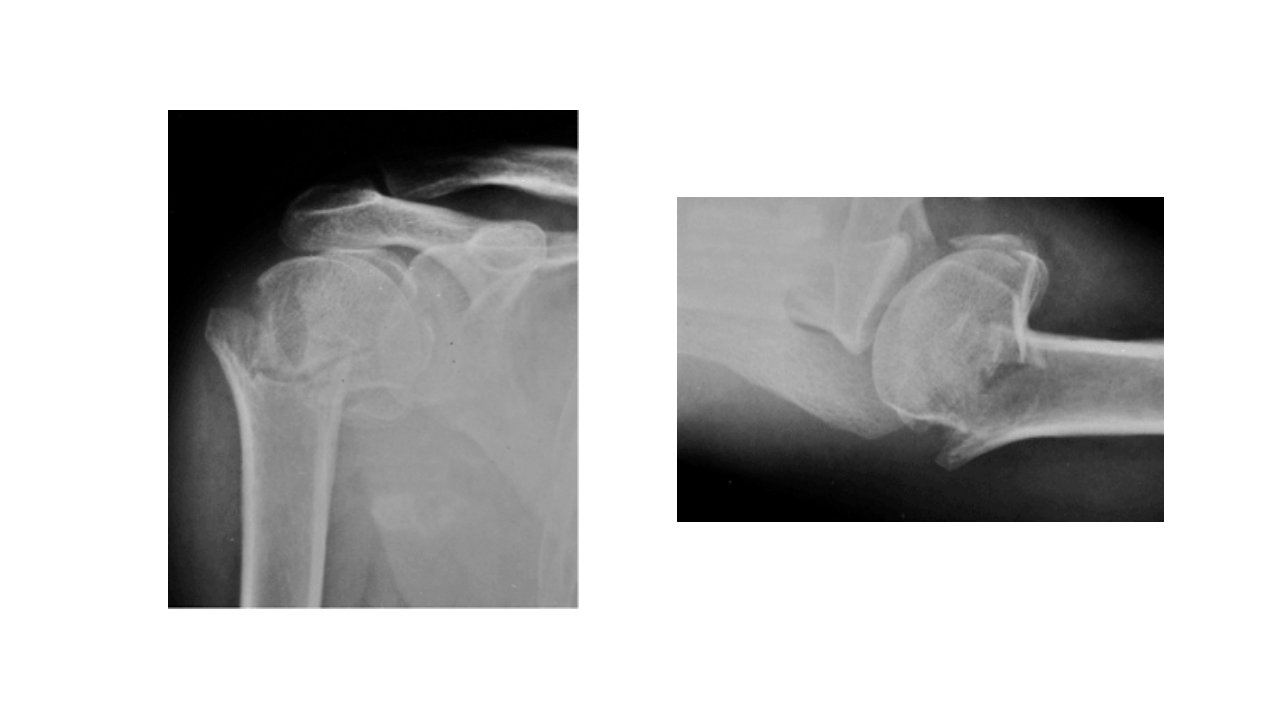

BUSINESS REPORT 肱骨外科颈骨折 汇报人:XXX 202X 汇报时间: 一 病史 主 二 解剖 要 三 病因 四 诊断和鉴别诊断 内 五 并发症 容 六 治疗 七 洗手巡回配合 (一) 病史 XXX,女,65岁,骨一科,+8床,391109,患者自诉不慎跌倒致 左肩部外伤疼痛,肿胀,活动受限,休息后无缓解,现来我院摄 X线片示:左肱骨外科颈骨折,予以收住入院。病程中无昏迷、 呕吐、畏寒发热。无逆行性遗忘。 (一) 病史 体温 36.4℃ 脉搏 76次/分 呼吸 20次/分 血压 100/80mmHg 一般情况 发育正常,营养良好,体型正常,神志清楚。皮肤、 粘膜温度正常,干燥,未见黄疸、皮疹或出血点。 患者于2012年10月8日9:00在臂丛神经阻滞麻醉下行左肱骨外科 颈切开复位内固定术,手术顺利,于10:...